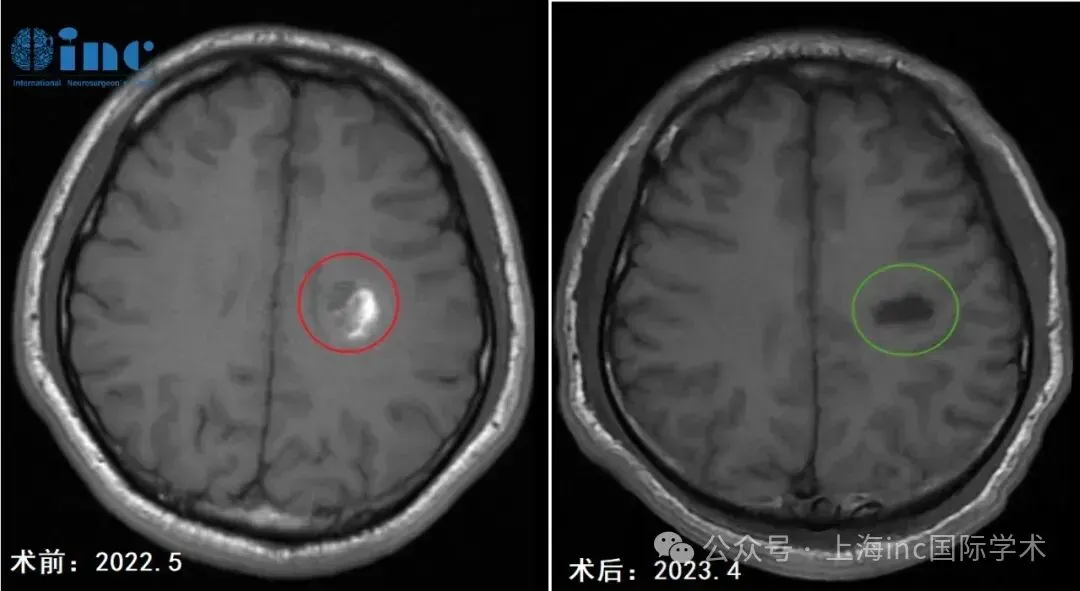

一年前,30岁患者阿勇出现右手握笔障碍,书写字迹逐渐扭曲,伴右侧肢体提重物时无力感。症状持续半月后就诊,MRI检查显示左侧半卵圆中心区存在8.0×11.0mm类圆形异常信号灶,初步诊断为功能区海绵状血管瘤。2022年5月MRI影像证实病灶处于急性出血期,提示若未及时干预,再次出血可能导致右手完全瘫痪及语言功能受损。

手术实施:神经导航辅助下的精准显微切除

术后当日评估显示患者吞咽与咳嗽功能正常,右上肢轻度无力,其余肢体活动无障碍。术后第四天可实现自主下床活动。根据临床规律,功能区海绵状血管瘤患者需经历短期(数周)生活自理能力恢复与长期(数月到一年)神经功能完全康复两个阶段。本例患者的快速康复得益于手术精准性及系统化术后康复训练。